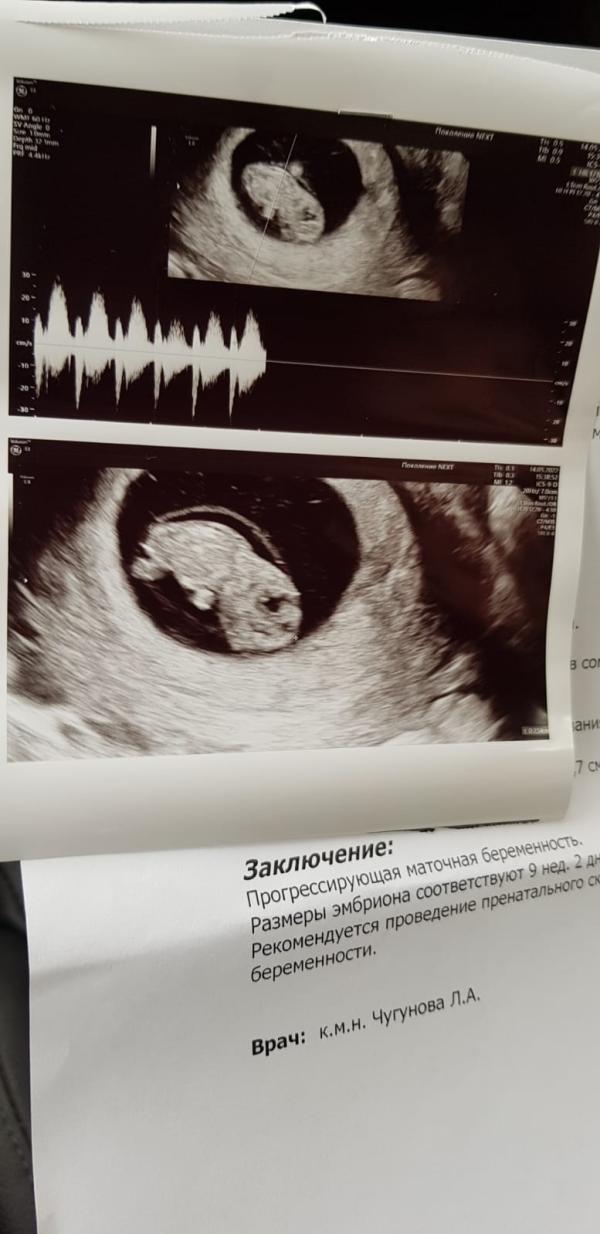

Наша бусинка подросла😍 9 неделек))) держись крепче малыш🙏♥️